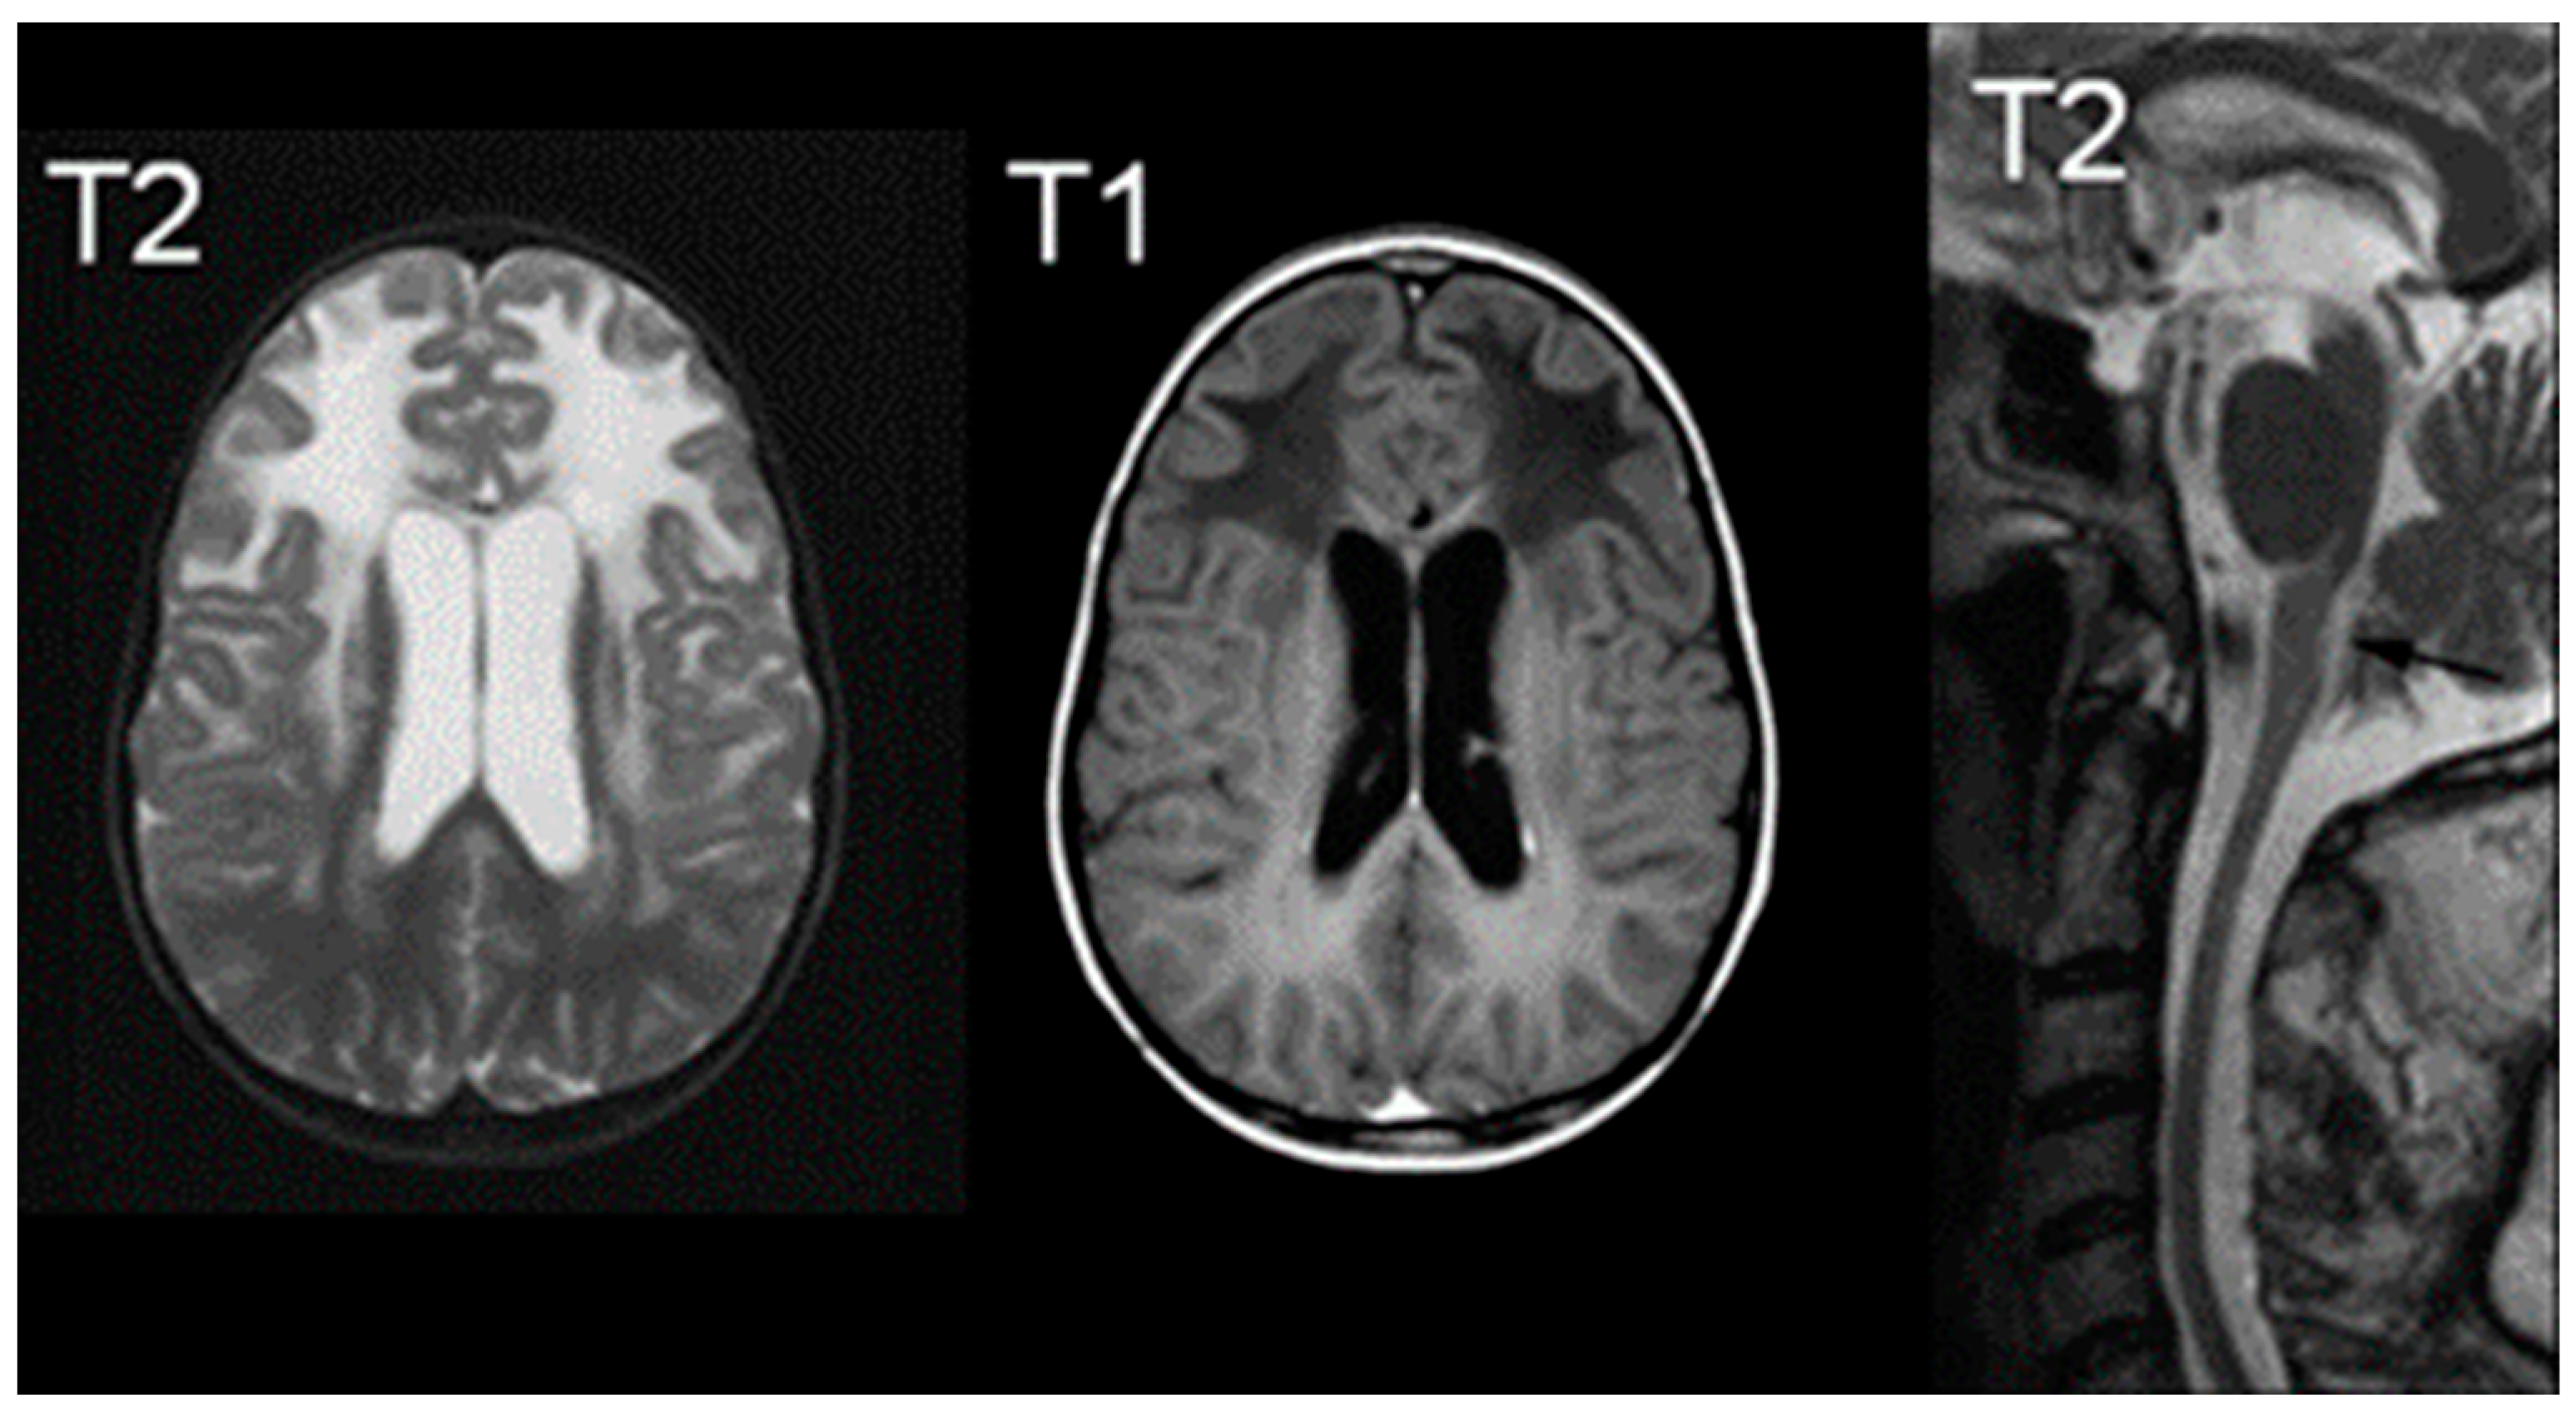

- McAdams, H.P.; Geyer, C.A.; Done, S.L.; Deigh, D.; Mitchell, M.; Ghaed, V.N. CT and MR imaging of Canavan disease. AJNR. Am. J. Neuroradiol. 1990, 11, 397–399. [Google Scholar] [PubMed]

- Hoshino, H.; Kubota, M. C anavan disease: Clinical features and recent advances in research. Pediatr. Int. 2014, 56, 477–483. [Google Scholar] [CrossRef] [PubMed]